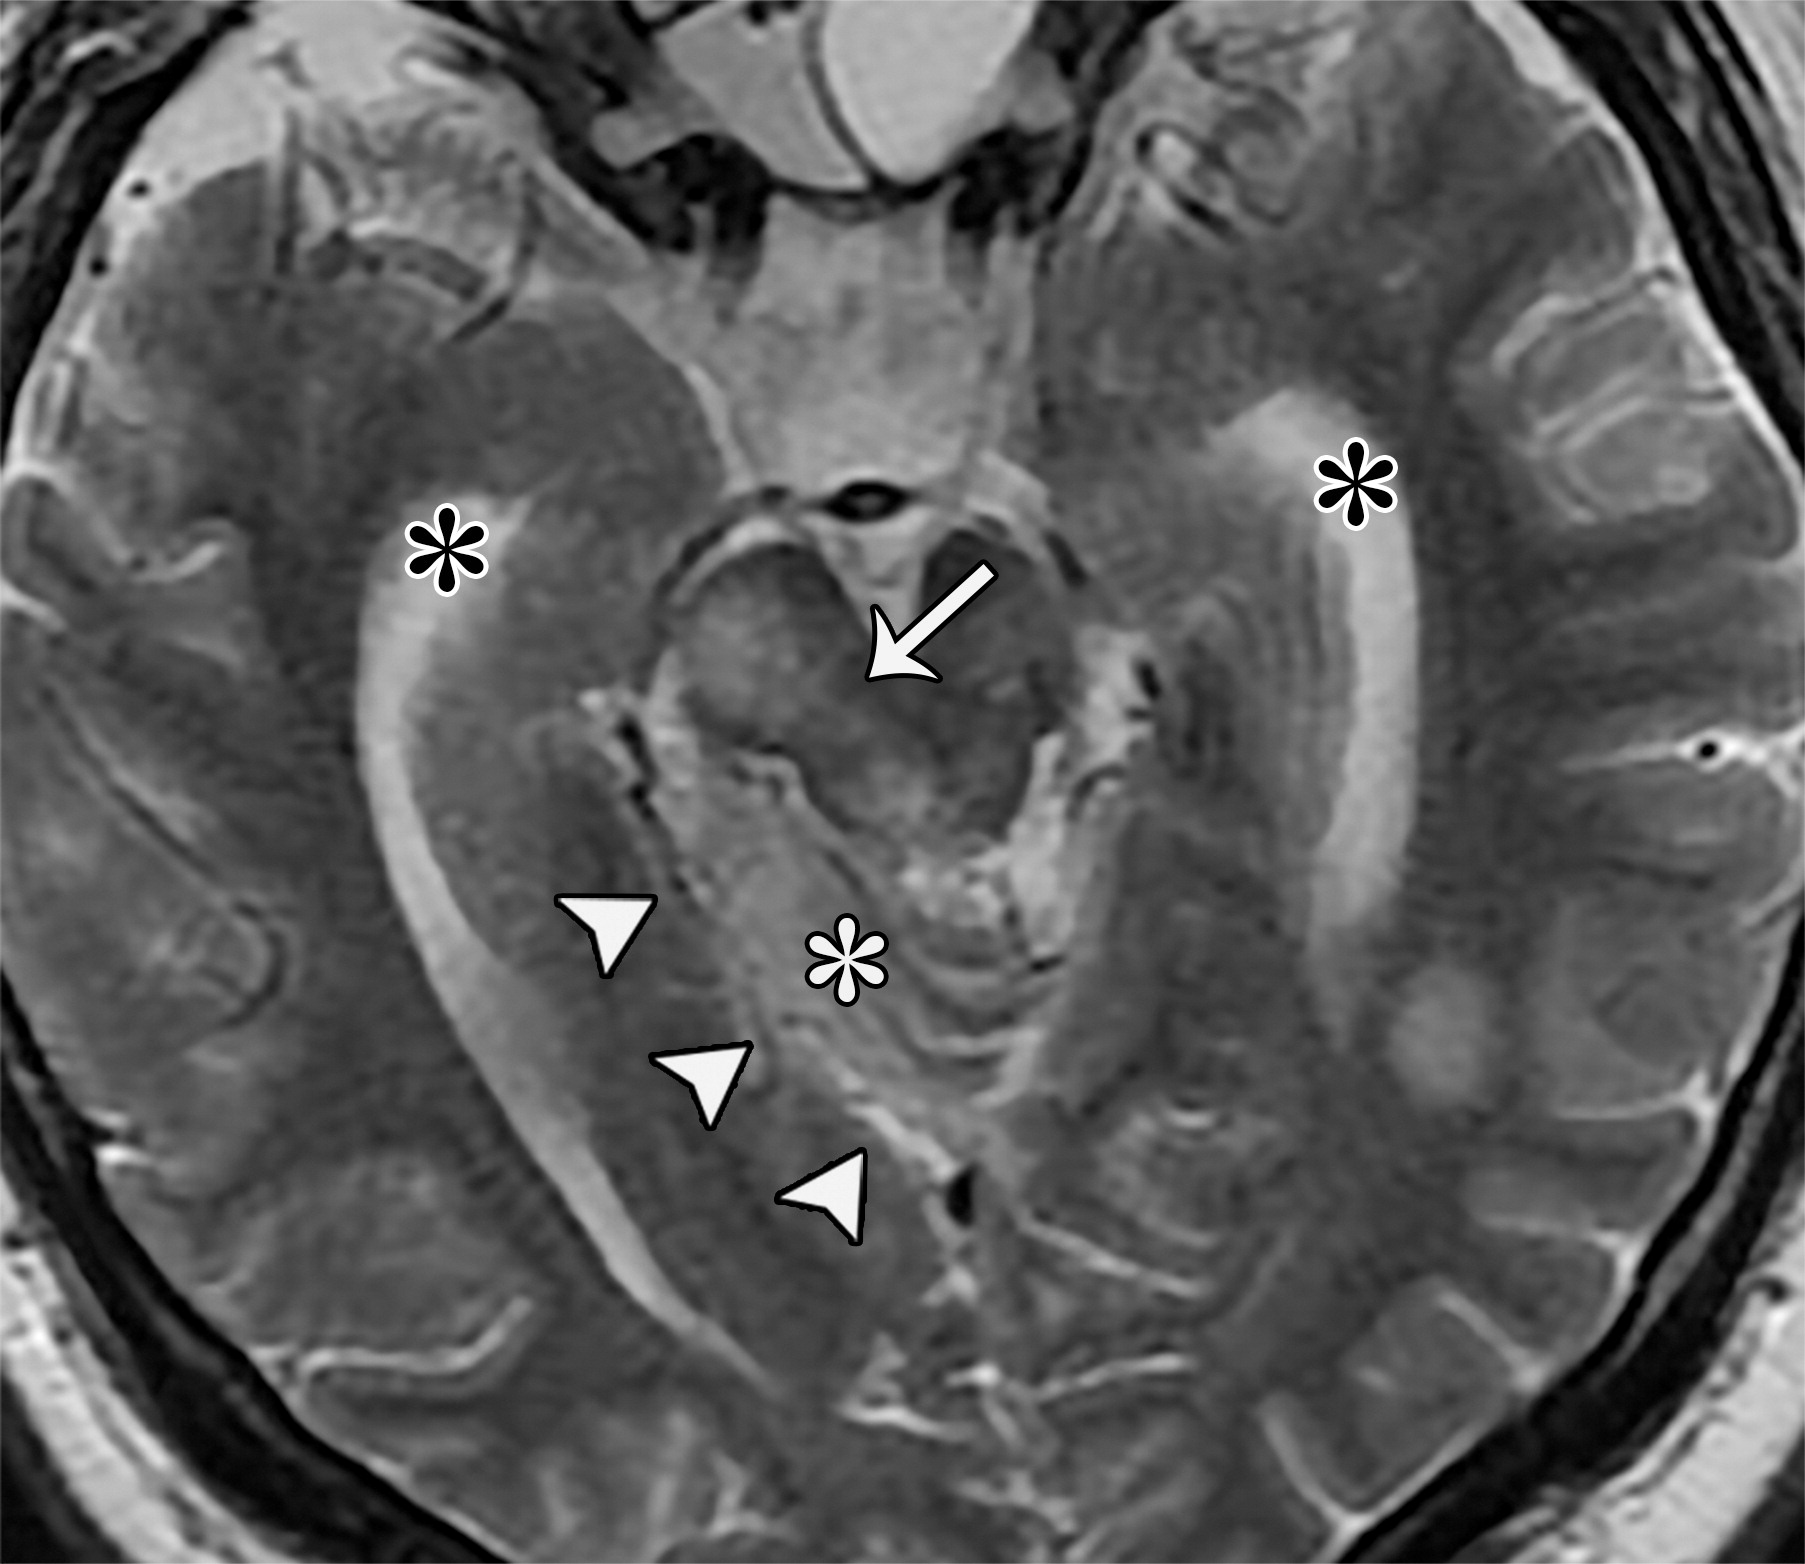

338eacde522c534fcbe30a562cfb64f4.jpeg

中脑导水管(白色短箭头),大脑后动脉(白色长箭头),大脑脚池(CrC),海马回(HG),大脑脚间池(IPC),中脑周围池(PMC),四叠体池(QC),钩回(U)。

2a4f468a04150c279dbe4187672a609d.jpeg